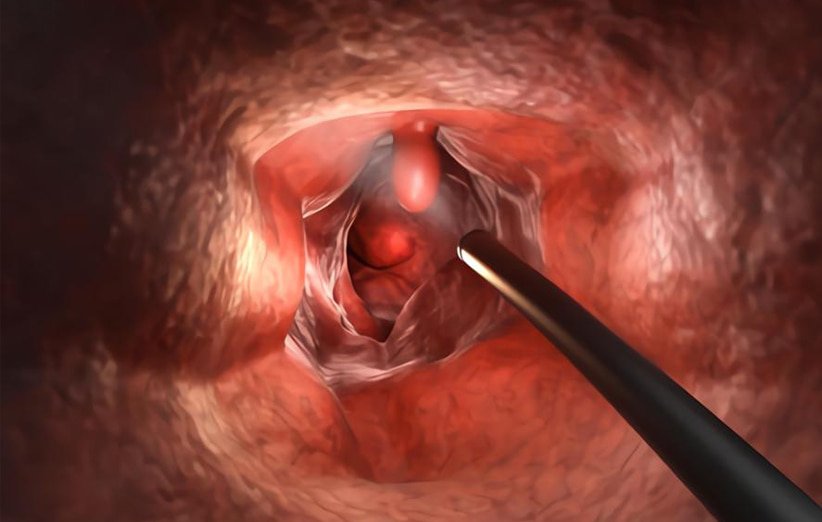

قیمت: 52٬500 تومان - دسته بندی فایل: فنی مهندسیدانلود پاورپوینت پولیپ معده Stomach polyps چیست

خرید پاورپوینت حرفه ای با موضوع پولیپ معده Stomach polyps چیست از لوکس فایل